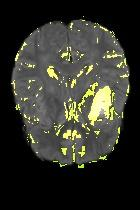

Current unsupervised anomaly localization approaches rely on generative models to learn the distribution of normal images, which is later used to identify potential anomalous regions derived from errors on the reconstructed images. However, a main limitation of nearly all prior literature is the need of employing anomalous images to set a class-specific threshold to locate the anomalies. This limits their usability in realistic scenarios, where only normal data is typically accessible. Despite this major drawback, only a handful of works have addressed this limitation, by integrating supervision on attention maps during training. In this work, we propose a novel formulation that does not require accessing images with abnormalities to define the threshold. Furthermore, and in contrast to very recent work, the proposed constraint is formulated in a more principled manner, leveraging well-known knowledge in constrained optimization. In particular, the equality constraint on the attention maps in prior work is replaced by an inequality constraint, which allows more flexibility. In addition, to address the limitations of penalty-based functions we employ an extension of the popular log-barrier methods to handle the constraint. Comprehensive experiments on the popular BRATS'19 dataset demonstrate that the proposed approach substantially outperforms relevant literature, establishing new state-of-the-art results for unsupervised lesion segmentation.